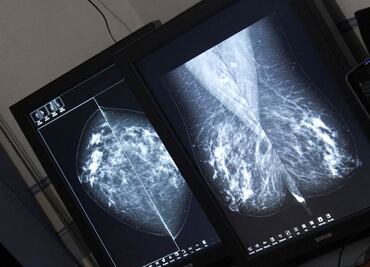

En el marco del Día Internacional de la Lucha contra el Cáncer de Mama, la mandataria arrancó la jornada intensiva “Tómatelo a pecho” de detección de esta patología por medio de la realización de mastografías gratuitas

Además, se otorgarán mil 200 atenciones más a mujeres mayores de 40 años, de aquí a noviembre próximo, en distintos puntos de la demarcación

“Recuerda que el cáncer de mama es curable si se detecta a tiempo”, invitó el Gobierno de la Ciudad de México

La secretaria de Salud, Oliva López Arellano, señaló que la detección temprana del cáncer de mama es fundamental para su atención oportuna, por ello recomendó a las mujeres hacerse este estudio a partir de los 40 años